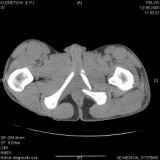

Уважаемые коллеги! Хотелось бы услышать совет по тактике лечения представлленого больного.Поступил после лечения в одном изотделений области. Травма 2,5 месяца назад. После выведенияиз шока был произведен остеосинтез перелома бедра, предплечья, до перевода к нам проводилосьвытяжение по оси шейки бедра за стержень, введенный в большой вертел. На сегодня деформацияригидна, клинически мобильности не определяется. Заранее признателен. P.S. Данный вид травм не включен в перечень "высокотехнологичных операций", направить длялечения по квотам Минздрава очень сложно.

Это обзорные и косые снимки

Привет, Леонид. Оскольчатый высокий двухколонный перелом в такие сроки трогать не надо, т.к. это про такие переломы сказано: "кто с ножом на Ж. пойдет тот в ней и останется...".